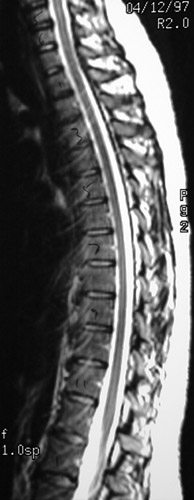

This is a normal sagittal MRI scan demonstrating the midline with the T1 vertebral body and T10 vertebral body and cauda equina.